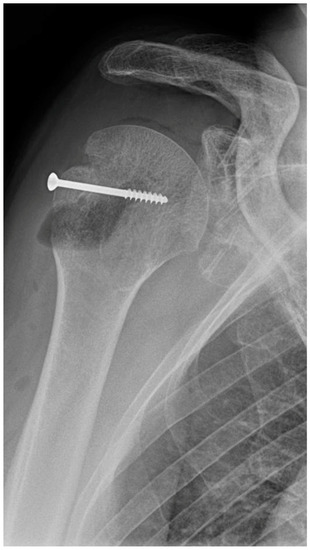

In an 81-year-old patient, four MAGNEZIX® CS screws (2.7 mm diameter) were used for osteosynthesis in a glenoid fracture after anterior shoulder dislocation. Here, material failure was seen in three of the four screws (Figure 3). At the follow-up examinations (3, 6 and 9 months), the patient was symptom-free, except for minimal pain (VAS 1).

Figure 3. Material failure of MAGNEZIX® CS screws used for osteosynthesis in a glenoid fracture after anterior shoulder dislocation.